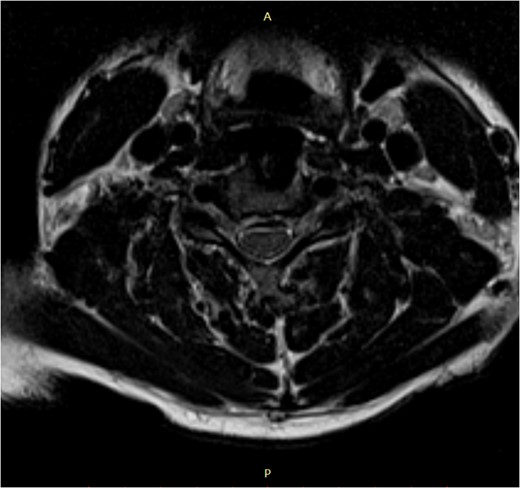

Pre-surgery axial MRI. Arrowhead points towards a focus of hyperintensity at the aforementioned level.